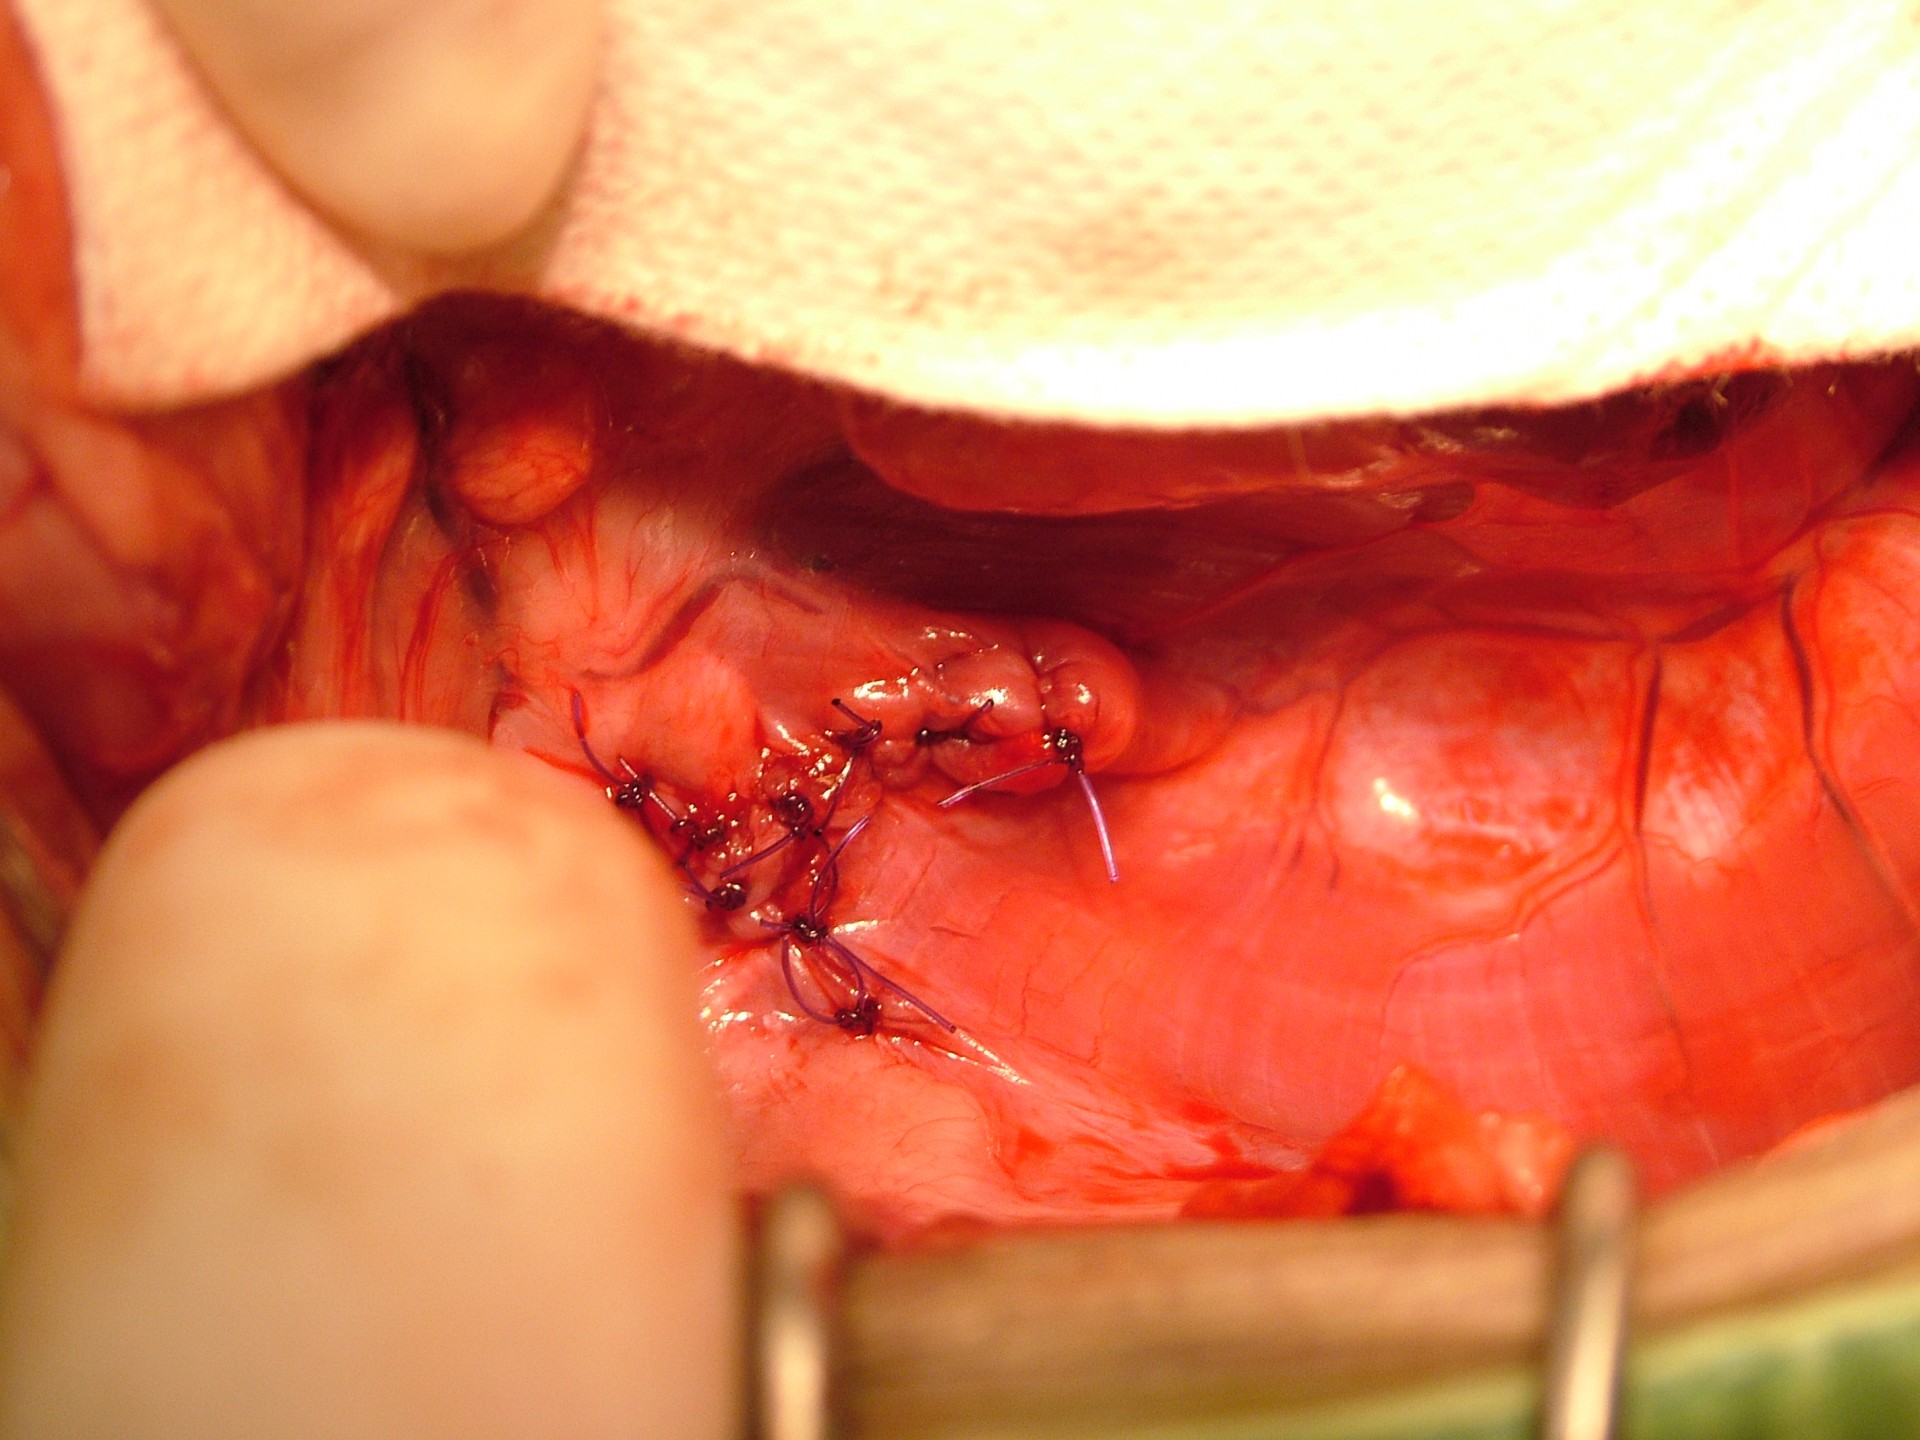

Mindhárom rekeszsérv forma meglehetősen ritkán fordul elő. A diagnózis felállítása a kórelőzmény, a klinikai tünetek a mellkas röntgenvizsgálata, a hasüreg ultrahangos vizsgálata alapján lehetséges.A rekeszsérv műtéti ellátása során a legnagyobb kihívást az jelenti, hogy a hasüreg megnyitását követően a sérvkapun keresztül levegő kerül a mellüregbe, ezáltal az állat spontán légzése leáll, így a műtét teljes ideje alatt asszisztált lélegeztetésre van szüksége.A műtét során a mellkasba előesett szerveket reponáljuk, a rekesz folytonosság hiányát megszüntetjük és a mellkasban lévő szabad levegőt eltávolítjuk, ezzel biztosítva az állat spontán légzését. A műtétet követő napokban legfontosabb feladat a vérkeringés és a légzés folyamatos, kórházi körülmények közötti kontrolálása.Az idejében felismert és megfelelően ellátott veleszületett rekeszsérv jó eséllyel gyógyítható, a traumás eredetű sérv ellátásának eredményességét általában az egyéb szervek sérülése határozza meg.